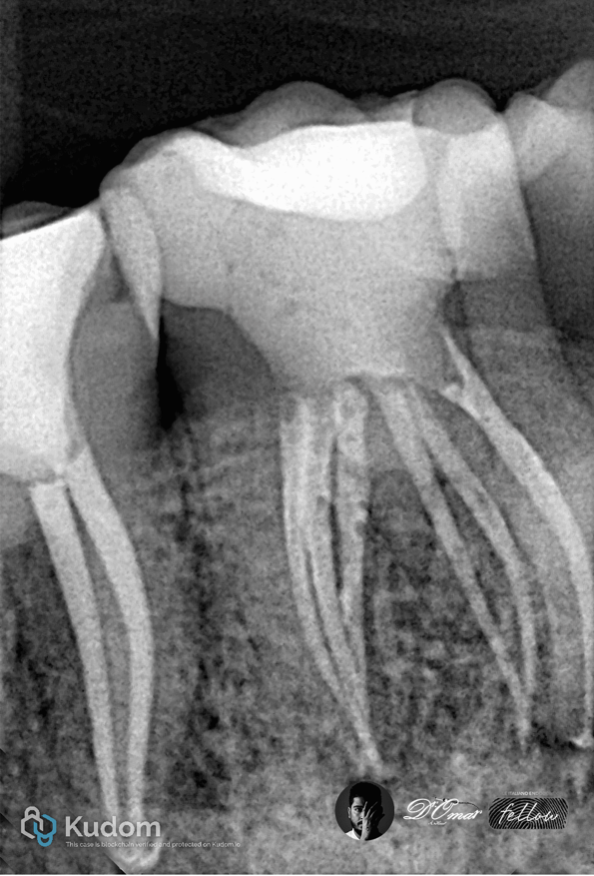

Fig. 2

Working length established using apex locator and radiographs

Rotary NiTi instrumentation to full working length

Irrigation using NaOCI with ultrasonic activation

EDTA for smear layer removal

Fig. 3

Obturation done by BC sealer

with warm vertical compaction